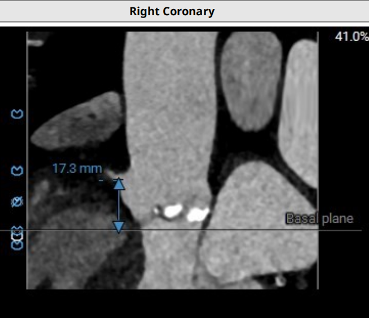

经升主动脉入路需评估升主动脉长度及钙化病变情况。

3.具备升主动脉入路条件:

a.升主动脉位于胸骨右侧;

b.使用自膨胀瓣膜,瓣环水平到升主动脉穿刺点大于70mm;

c.升主动脉穿刺点无明显钙化。